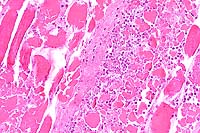

20x

obj

- Case 7-3. Placenta. Trophoblastic cells are detached

from the surface of the fetal placenta and placenal villi. The

intervillus space contains abundant necrotic cellular debris,

scattered yellow-orange pigment (meconium), and occassional macrophages

and neutrophils. Villous connective tissue is thickened and hyalinized.

40x

obj H&E

- Case 7-3. Lung. There are abundant coccobacilli

and fewer neutrophils filling scattered bronchioles. Occassional

plump macrophages contain bacteria which compress the nucleus

against one pole of the cell. The interstitium is expanded by

macrophages, fewer lymphocytes and fibroblasts admixed with finely

granular proteinaceous debris.

obj B&H stain

- Case 7-3. Lung. Brown and Hopps staining demonstrate

aggregates of Gram positive bacilli within many of the bronchioles.

Periarteriolar connective tissue is expanded by clear space (edema).